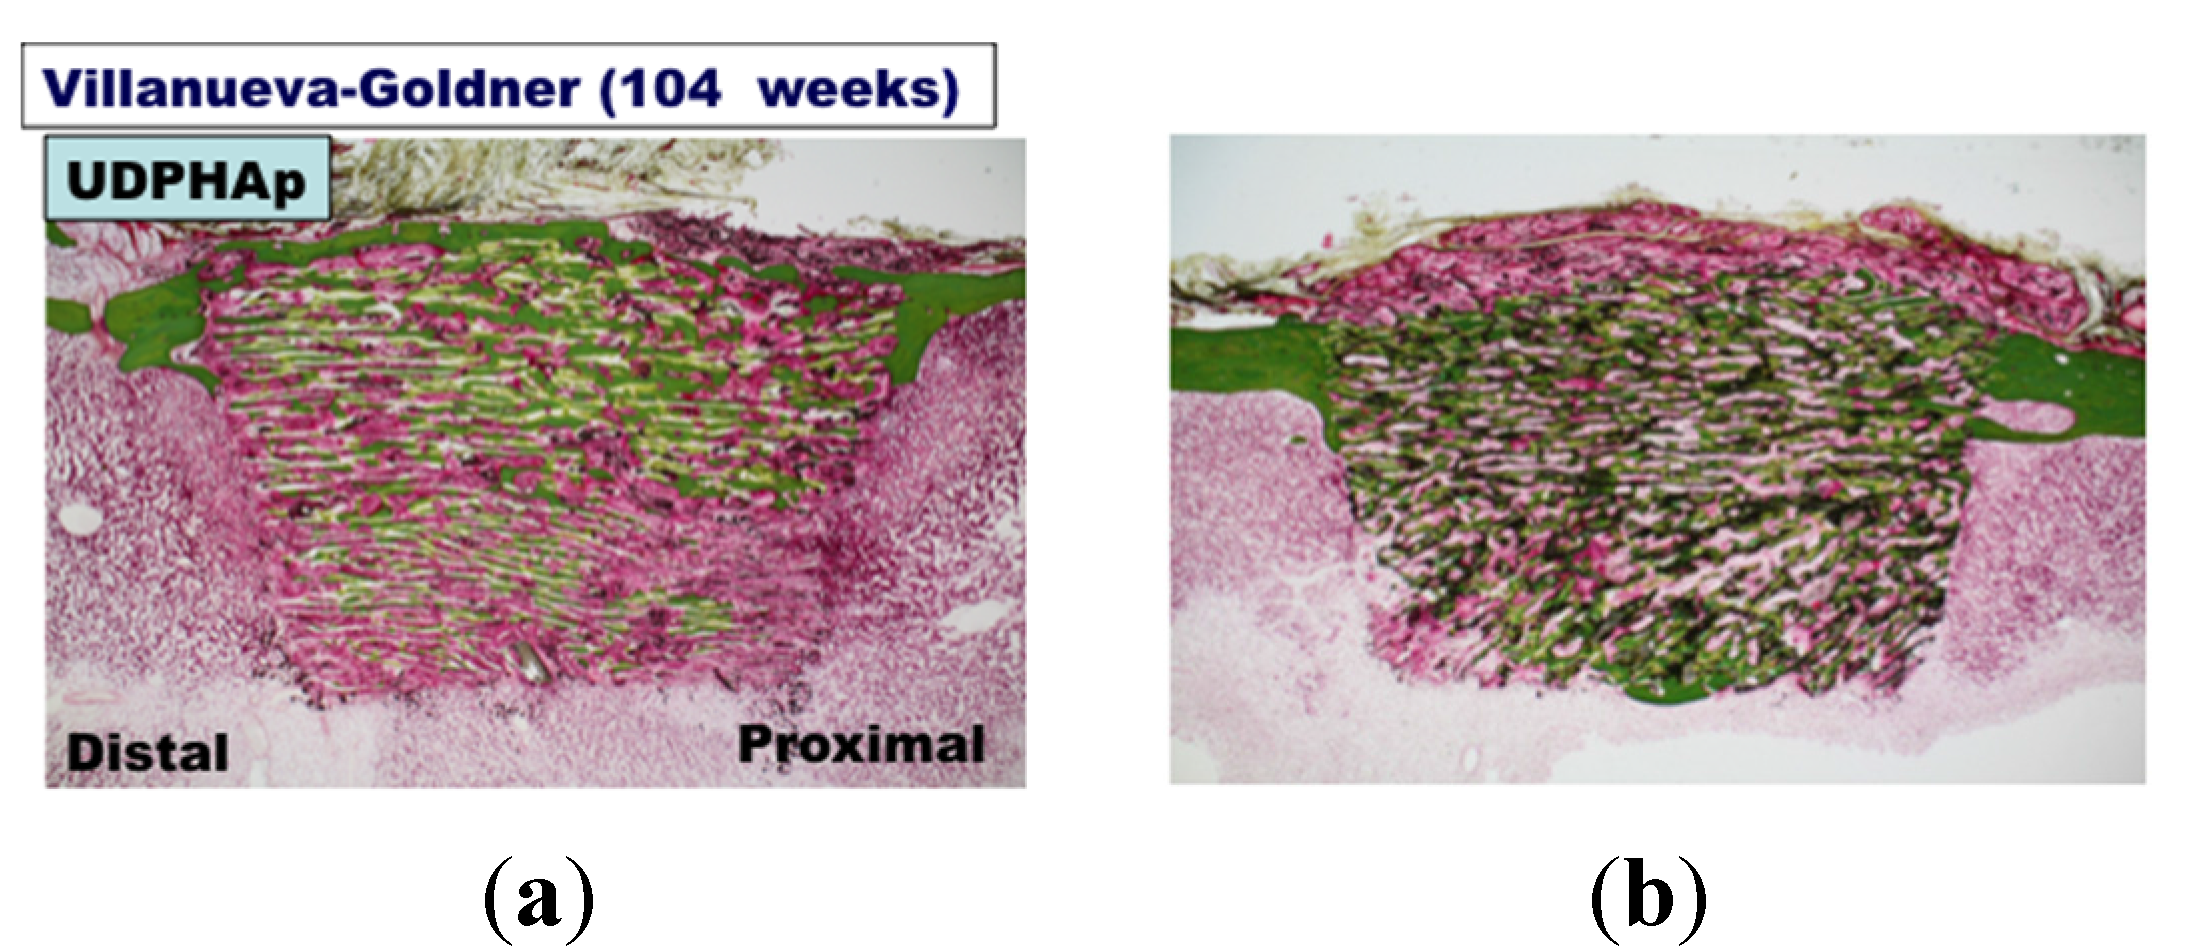

2. Results and Discussion

3.3. Bone Formation in Cortical and Medullary Bone Regions